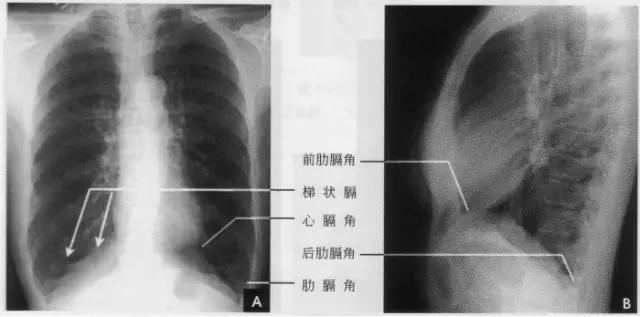

在正位胸片上,膈显示为圆顶状阴影,边缘光滑整齐,顶峰靠近中内1/3处。内侧与心脏形成心膈角。外侧与胸壁相交形成肋膈角;在侧位片上,圆顶部靠前,前端与前胸壁形成前肋膈角,后部与后胸壁形成后肋膈角,正常时前、后肋膈角均为锐角,后肋膈角位置最低。右膈顶的位置,一般与第6前肋或第10后肋等高,多数人右膈比左膈高1~2cm,这是因为心脏位置偏于胸腔左侧,故而将左膈压低。膈的位置在正常时可有若干变动:例如儿童膈位置较高,老年人则较低;矮胖型膈位置较高,瘦长型则较低;卧位时膈位置较高,立位时则较低;呼气时膈位置较高,吸气时则较低等。

③梯状膈。深吸气时膈面出现数个呈梯状排列、尖端引向外上方的突起影,这是由于附着于各前肋端的膈面被肋骨过度牵引所致(如下图)。